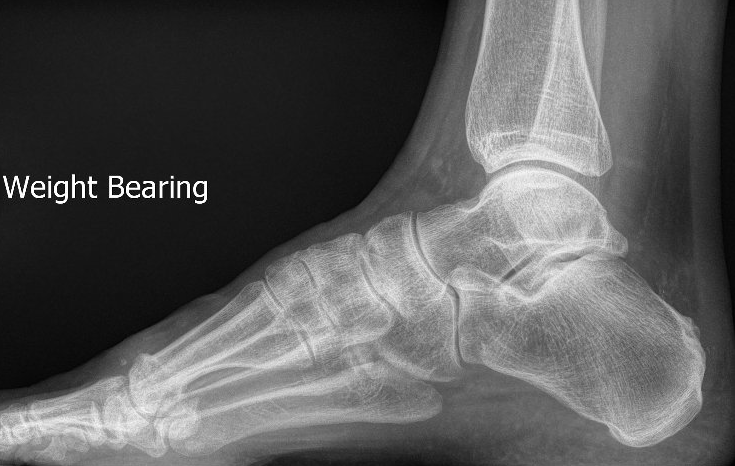

- high arched (cavo-varus) feet (see image below)

- weight-bearing X-rays of the ankle and foot